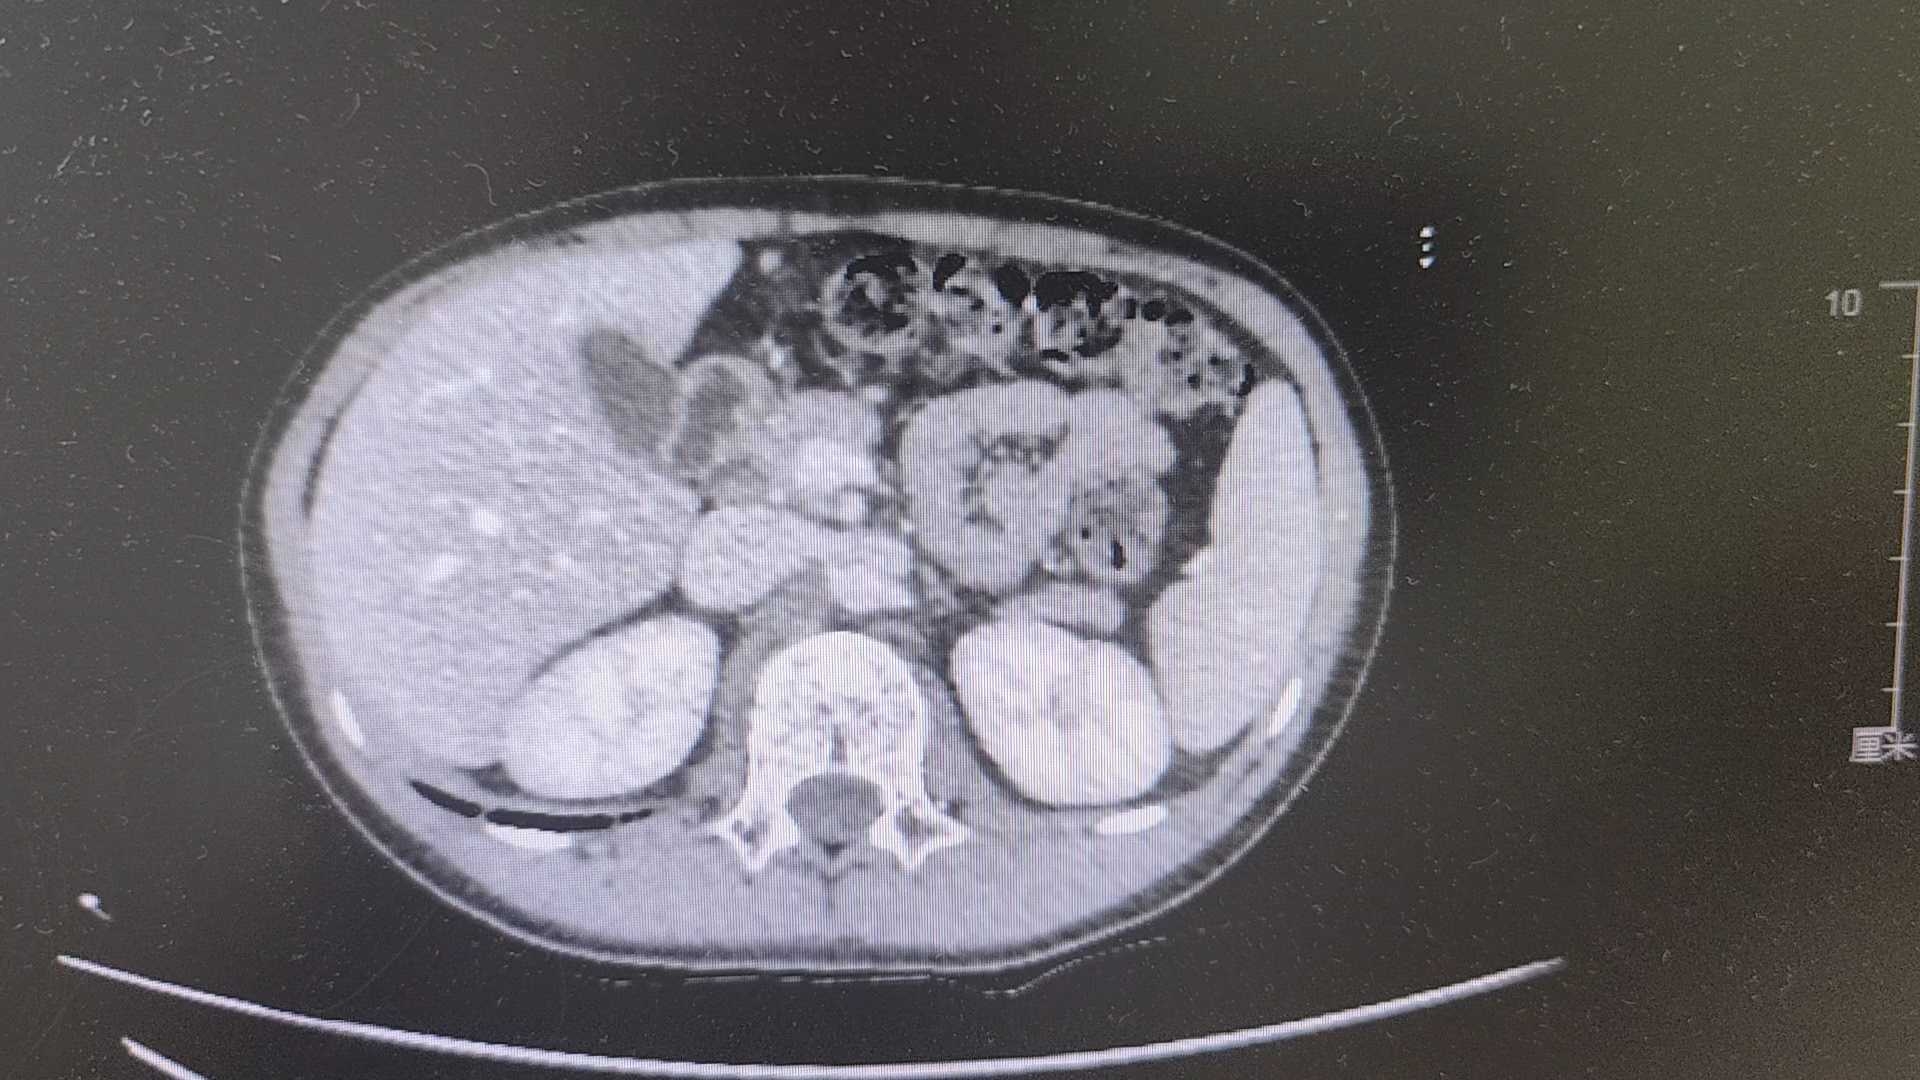

【检查】:

【临床诊断】:1.消化道出血,美克尔憩室?2.中度贫血3.腹腔积液